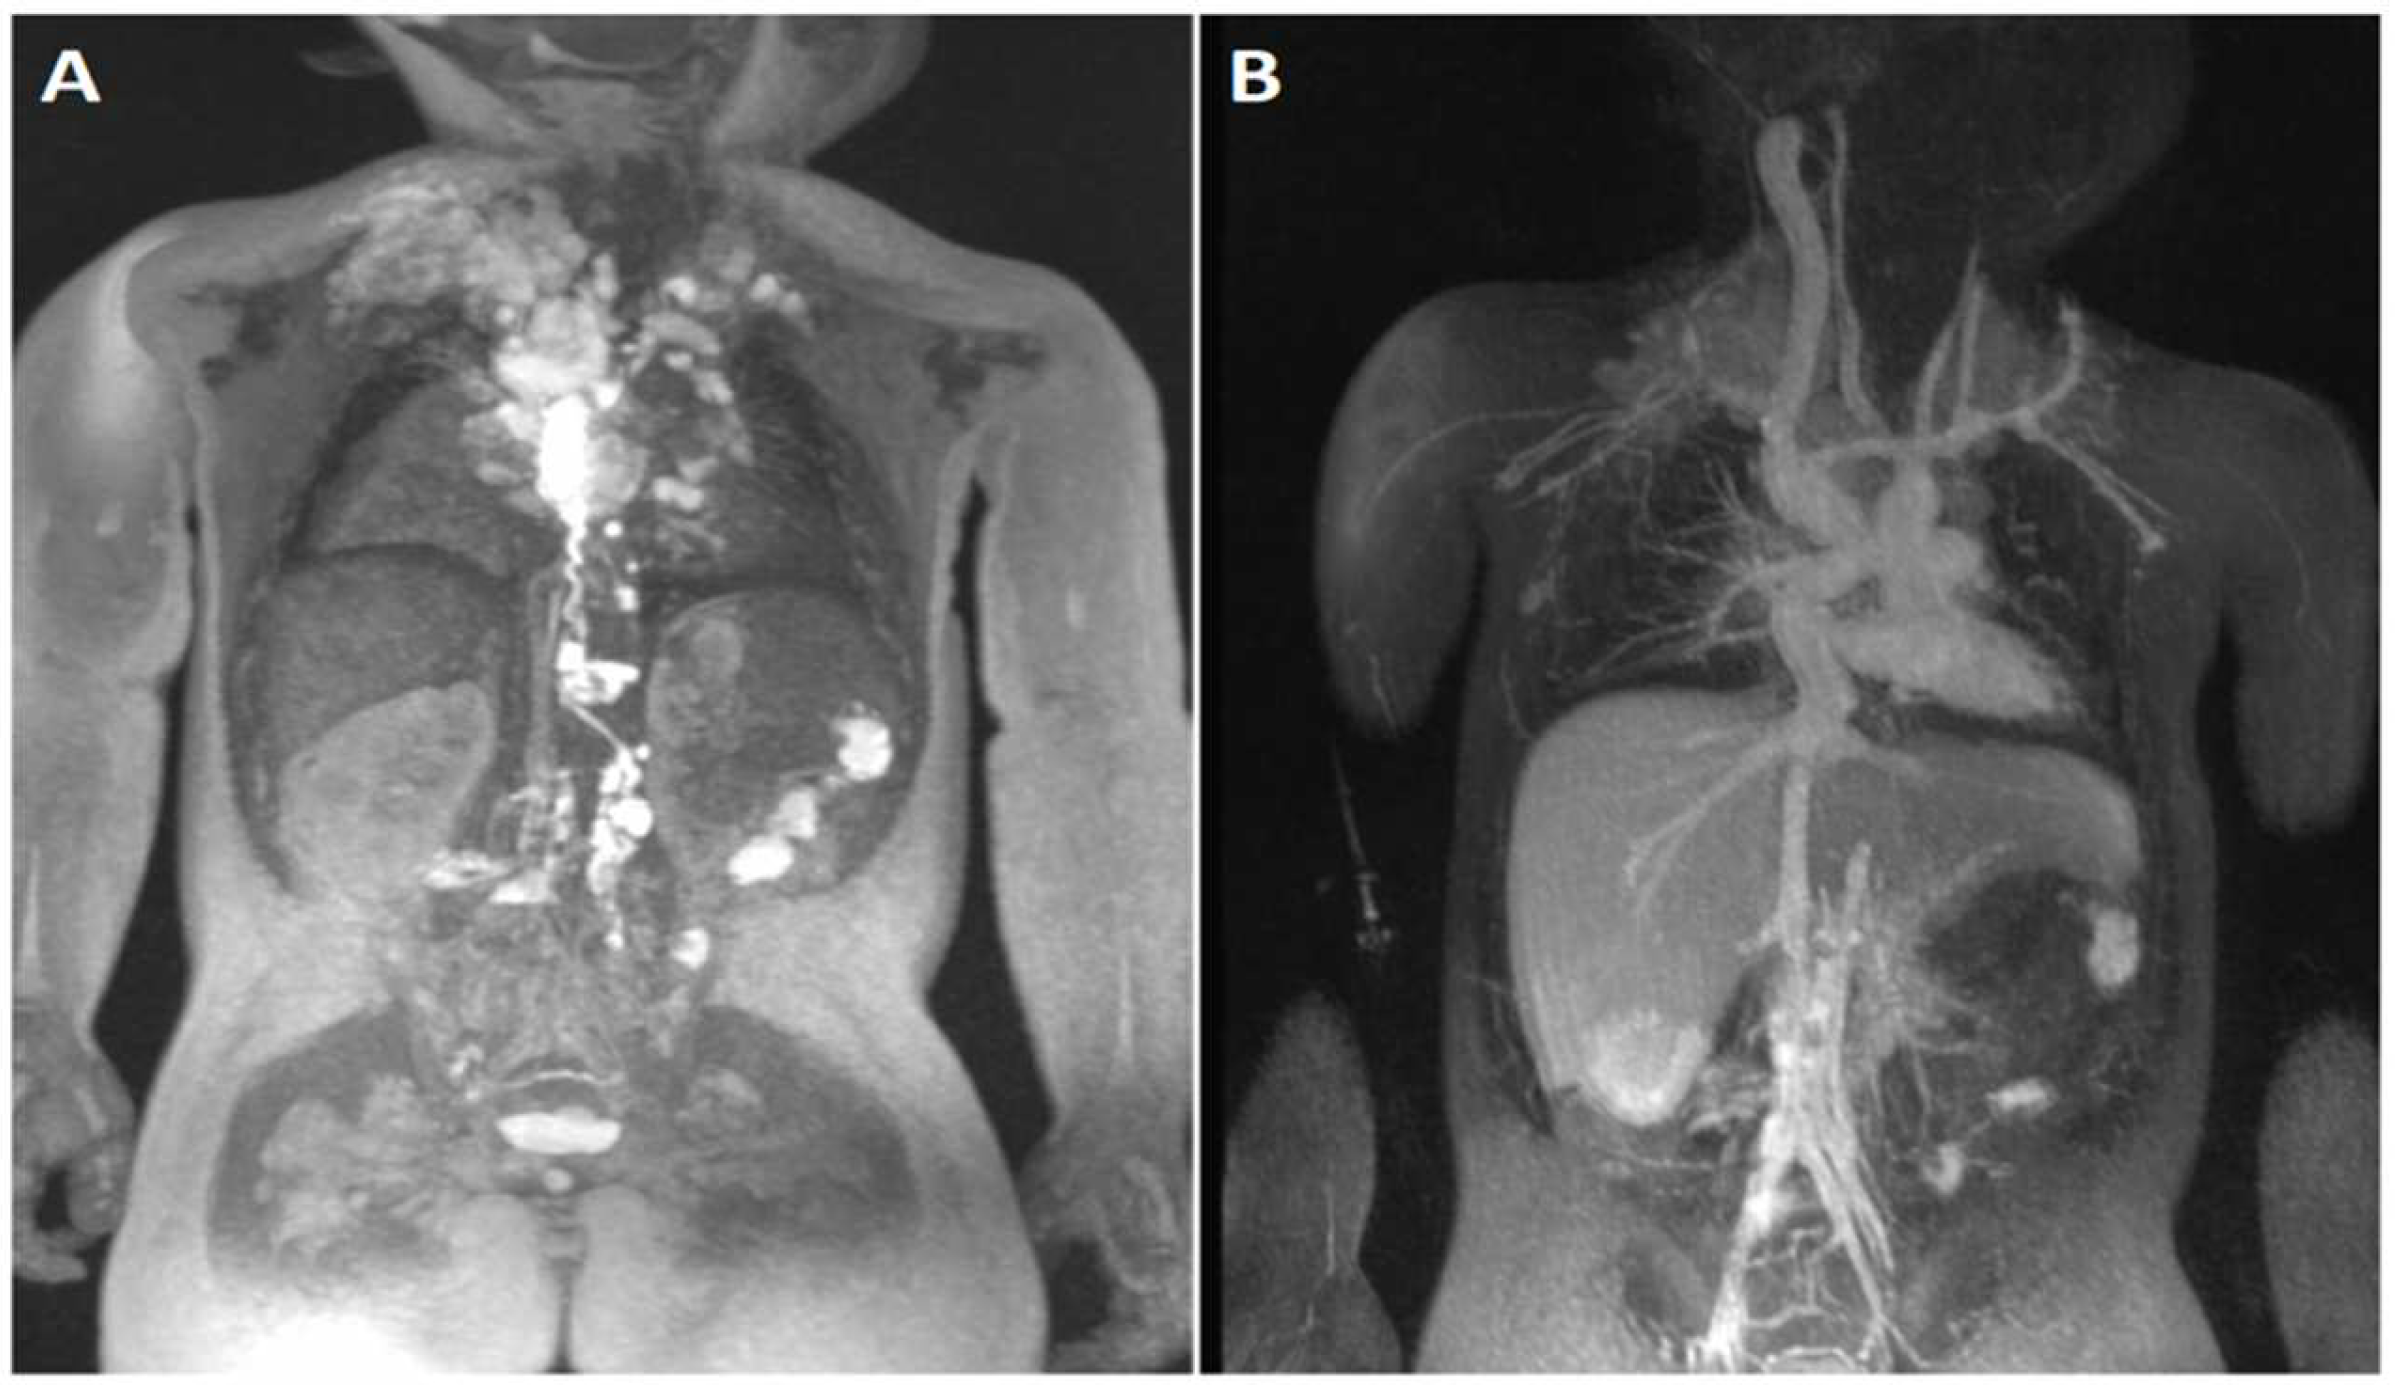

4.5. Lymphatic Imaging

| Lymphatic Imaging | Overlay of FE MRA and contrast-enhanced MRL images has allowed high-resolution comprehensive mapping of the vascular tree as it relates to abnormal lymphatic connections in patients with conditions such as chylothorax, protein losing enteropathy, and plastic bronchitis. These imaging techniques have facilitated the development of novel transcatheter treatments. |